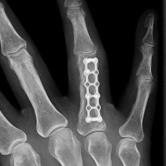

Röntgenbilder

4) Strecksehnenverletzungen der Hand

Die Strecksehnen im Bereich der Hand werden über viele Zügel und Querverbindungen gesichert, somit sind Strecksehnenverletzungen deutlich weniger problematischer als Beugesehnenverletzungen. Im Streckerbereich ist häufig, trotz Verletzung der Sehnenstruktur, noch eine aktive Streckung über Seitzügel möglich. Bei sicherer Durchtrennung eines Teils des Streckapparates wird häufig eine direkte Naht durchgeführt, die Nachbehandlung ist weniger aufwendig und kürzer als im Bereich der Beugesehnen.Strecksehnenverletzungen in Höhe des Endgelenkes sind relativ häufig, auch im Rahmen von spontanen Rissen durch forcierte kraftvolle Beugung im Endgelenk möglich. Hier kann meist eine konservative Behandlung mit Ruhigstellung in einer speziellen Plastikschiene erfolgen. Diese Plastikschiene (Stack'sche Schiene) muss dann über 6-8 Wochen konsequent getragen werden, damit der Strecksehnenansatz in Höhe des Endgelenkes vernarben kann.